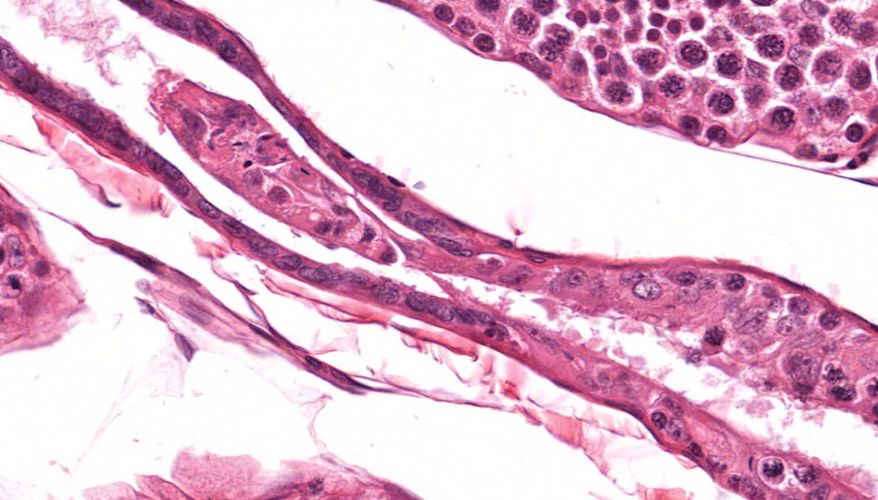

低倍镜:睾丸表面为鞘膜覆盖,其上皮为单层扁平上皮,鞘膜下是一层较厚的致密结缔组织,叫做白膜。白膜在睾丸后缘增厚,形成睾丸纵隔,其内可见不规则的腔隙,即睾丸网。睾丸内可见很多上皮性管道的切面,即生精小管的切面,呈圆形或椭圆形,管壁较厚,由生精上皮及其明显的基膜等组成。高倍镜:着重观察生精小管和其之间的睾丸间质。生精小管主要由生精上皮构成。生精上皮由生精细胞和支持细胞组成。生精细胞是一组细胞,依次自基膜向管腔面排列。

2.白膜

13.直精小管

14.睾丸网